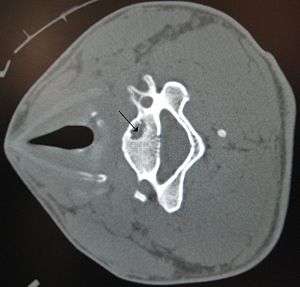

A bone cyst in the vertebra of the neck as seen on CT

A bone cyst or geode is a cyst that forms in bone.